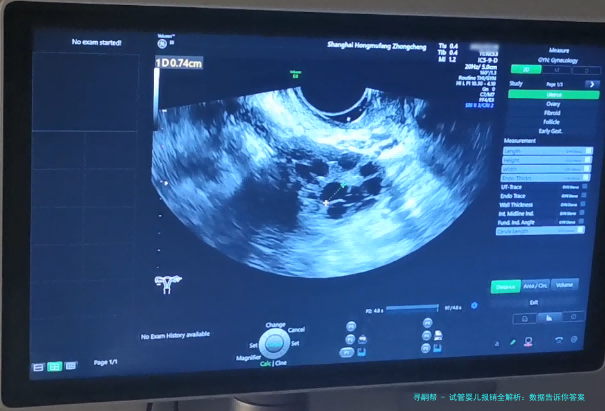

试管婴儿,医学上称为体外受精-胚胎移植,说白了就是把卵子和精子在实验室里结合,再放回妈妈子宫里。这技术在中国已经挺成熟了,据国家卫健委的数据,2020年中国试管婴儿周期数超过100万例,比2015年增长了近50%,这背后反映出需求的激增和技术的普及。不过,费用问题一直是拦路虎,普通家庭得攒好一阵子钱才能负担得起。